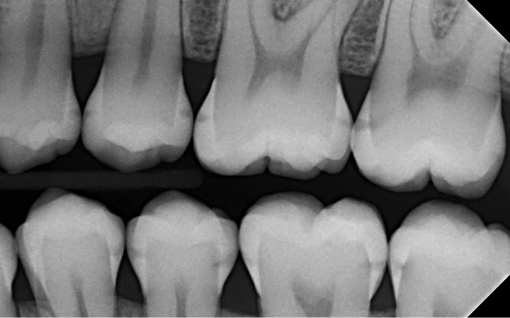

1. What surface require restoration?